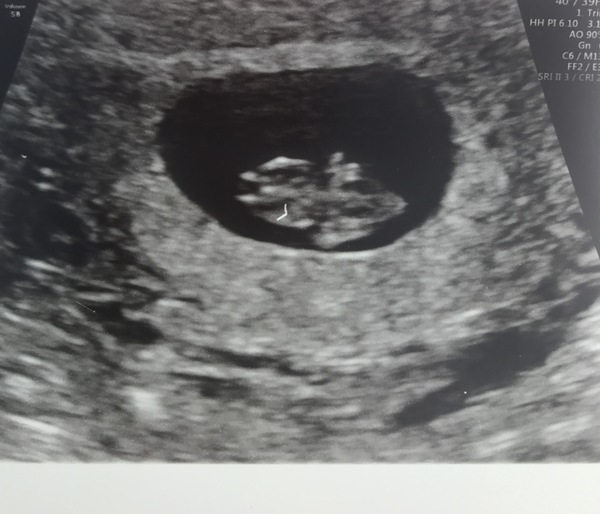

Lots of you asking about early scan pics - here is my little bean! All in top right, the biggest part is yolk sac and the solid white bit above is the head! 😍

Babies due in April 2018

starsshinebright · 25/08/2017 23:02

Measuring 8+2 Smile

@Jenster17 and @starsshinebright look at your little beans! I want a scan now! Starshine, yours looks like a space ship!!!

Haha finch, i think it looks like a frog!